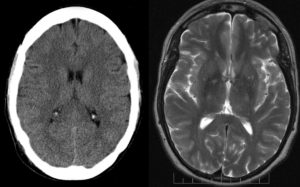

Острые нарушения мозгового кровообращения

Чаще всего в острейшем периоде для постановки диагноза инсульта применяется компьютерная томография. МРТ исследование же дает информацию о состоянии головного мозга уже после проведенной экстренной терапии.

Однако МРТ является более чувствительным методом диагностики, раньше выявляет очаг поражения.

При ишемическом инсульте очаг с высоким сигналом соответствует определенной зоне кровоснабжения (чаще в бассейне средней мозговой артерии).

На картине диффузионно-взвешенного изображения изменения могут быть выявлены еще до того, когда они станут заметны в других режимах, в виде повышенного осмоса. При геморрагическом проявляется гиподенсивным сигналом в режиме T1 и гиперденсивным сигналом в режиме T2, возможен масс эффект.

Субарахноидальное кровоизлияние выглядит на МР томограмме как очаг в форме серпа, окаймляющий большой полушарие, повторяющий его борозды и извилины, оттесняя нервную ткань с возможным сдавлением желудочков и гидроцефалией.

Инсульт.

Специалисты выделяют два вида острого нарушения мозгового кровообращения: в первом из них процесс инициирует ишемия тканей (кислородное голодание) в результате резкого ангиоспазма, тромбоза или эмболии, во втором — причиной становится разрыв сосудистой стенки с излитием крови и формированием гематомы. МРТ позволяет дифференцировать эти состояния. Зона, пострадавшая от гипоксии, имеет более светлый оттенок, а при геморрагическом инсульте видны разрывы сосудов (в отдаленный период на томограммах это выглядит, как темные полости с кольцевидными периферическими полосами).